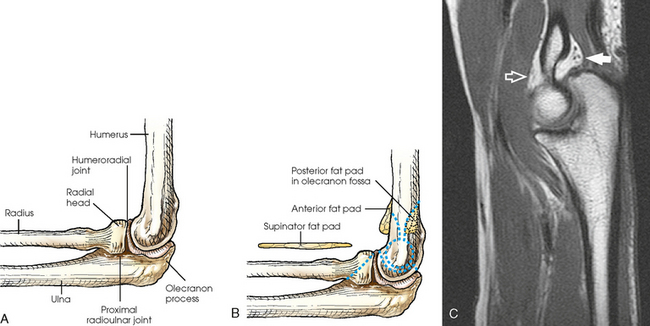

The elbow joint proper includes the proximal radioulnar articulation and the articulations between the humerus and the radius and ulna. The three joints are enclosed in a common capsule. The trochlea of the humerus articulates with the ulna at the trochlear notch. The capitulum of the humerus articulates with the flattened head of the radius. The humeroulnar and humeroradial articulations form a synovial hinge joint and allow only flexion and extension movement (Figs. 4-10 and 4-11, A). The proximal humerus and its articulations are described with the shoulder girdle in Chapter 5.

The three areas of fat1,2 associated with the elbow joint can be visualized only in the lateral projection (Fig. 4-11, B and C). The posterior fat pad covers the largest area and lies within the olecranon fossa of the posterior humerus. The superimposed coronoid and radial fat pads, which lie in the coronoid and radial fossae of the anterior humerus, form the anterior fat pad. The supinator fat pad is positioned anterior to and parallel with the anterior aspect of the proximal radius.

When the elbow is flexed 90 degrees for the lateral projection, only the anterior and supinator fat pads are visible, and the posterior fat pad is depressed within the olecranon fossa. The anterior fat pad resembles a teardrop, and the supinator fat pad appears as shown in Fig. 4-11, B. The fat pads become significant radiographically when an elbow injury causes effusion and displaces the fat pads or alters their shape. Visualization of the posterior fat pad is a reliable indicator of elbow pathology. Exposure factors designed to show soft tissues are extremely important on lateral elbow radiographs because visualization of the fat pads may be the only evidence of injury.